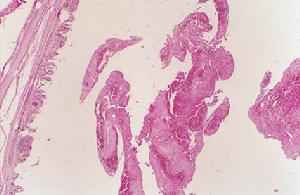

耳鼻咽喉白喉1、局部病變

白喉桿菌侵入人體組織後產生一種外酶素,損害黏膜上皮細胞,發生壞死,纖維素及白細胞滲出,纖維素凝固後,形成一層假膜,白喉桿菌在假膜下繁殖滋長,產生更多外黴素,所致病損擴大,假膜向四周蔓延,喉部假膜附著較松,有時可咳出。